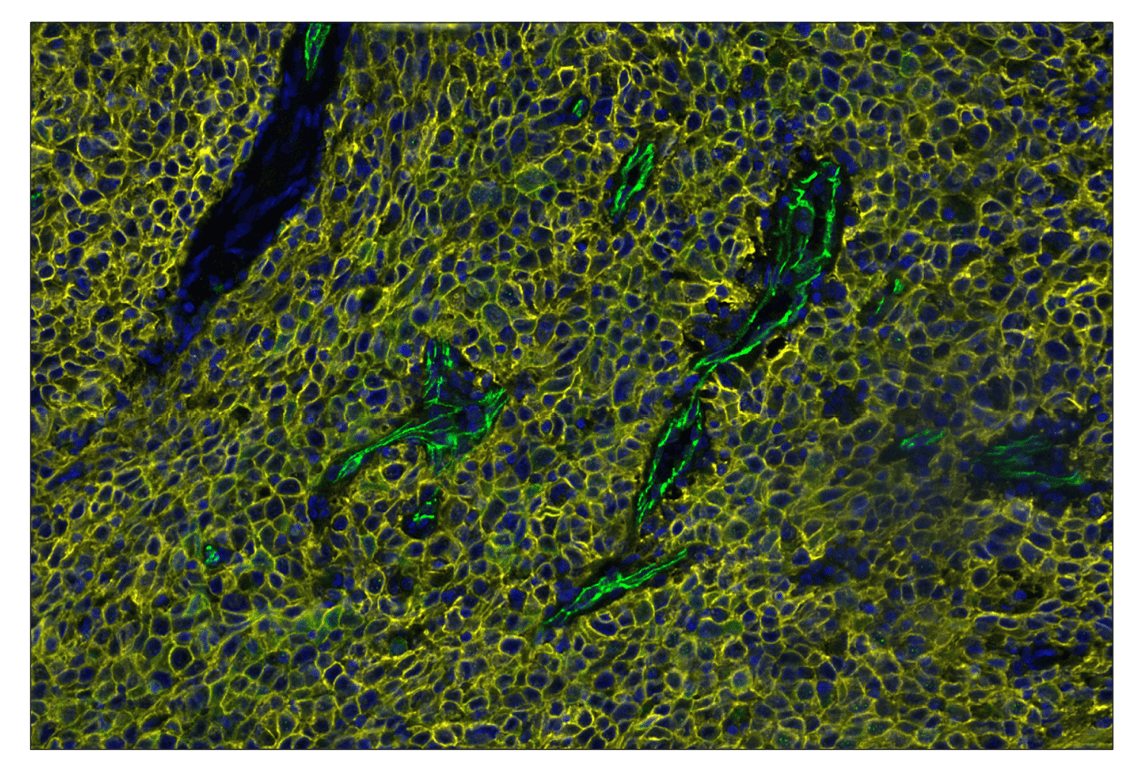

SignalStar™ multiplex immunohistochemical analysis of paraffin-embedded human squamous cell carcinoma of the cervix using VE-Cadherin (E6N7A) & CO-0149-488 SignalStar™ Oligo-Antibody Pair #53594 (green), TACSTD2/TROP2 (F4W4J) & CO-0150-594 SignalStar™ Oligo-Antibody Pair #90680 (yellow), and DAPI #4083 (blue). All fluorophores have been assigned a pseudocolor, as indicated.

Immunohistochemistry Image 4: TACSTD2/TROP2 (F4W4J) & CO-0150-488 SignalStar<sup>™</sup> Oligo-Antibody Pair